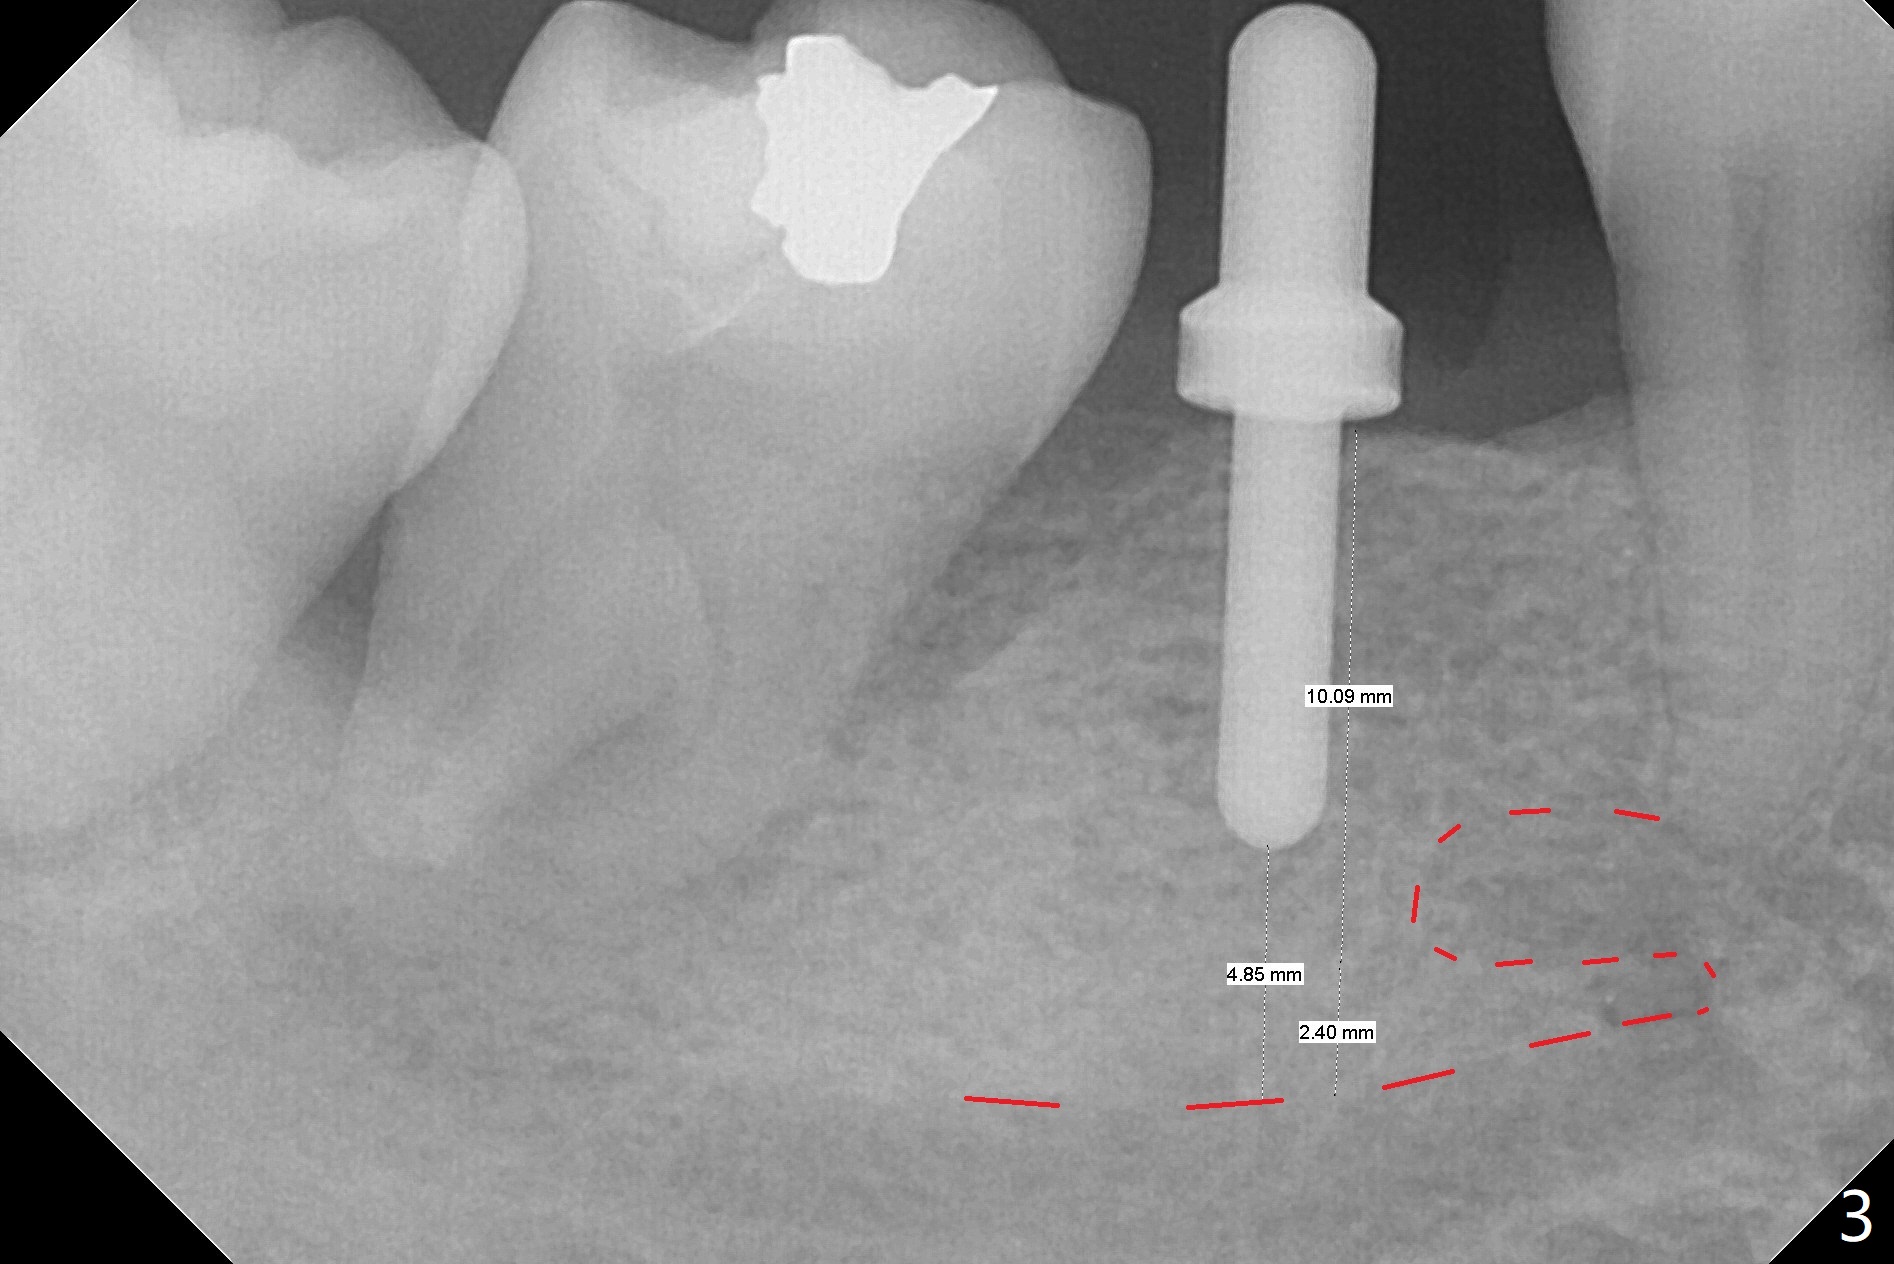

The ridge at #30 is not so narrow (Fig.1). Initial depth is 10 mm with 2 mm from the Inferior Alveolar Canal (Fig.2,3 red dashed line). A 4.5x10 mm implant is placed with > 50 Ncm; a 6.2x5(3) mm healing abutment placed (Fig.4). The implant is stable and seems to be ready for impression 3 months postop (Fig.5). CT taken 5 months post cementation shows that the implant could be placed more lingually (Fig.6 (coronal section; B: buccal)). Periradicular radiolucency at #31 (Fig.7 *) is continuous with the Inferior Alveolar neurovascular bundle (N). After extraction, care should be taken to remove granulation tissue. The tooth #32 will be extracted simultaneously because of severe bone loss.